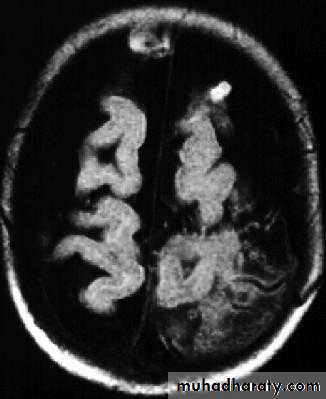

Bacterial Meningitis with cerebral oedema

Bacterial Meningitis with suppuration